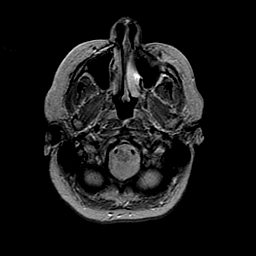

MR Study #2 -- Slice #8

[Home][Help][Clinical][Tour 1][Tour 2][Tour 3] Slice 8